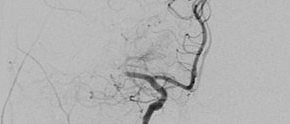

Mit Hilfe der Digitalen Subtraktionsangiographie (DSA) werden die Arterien über einen Katheter, der über die Leistenschlagader eingebracht wird und bis in die Halsgefäße navigiert mit  jodhaltigem Kontrastmittel sichtbar gemacht. Die Angiographieanlage macht dabei eine Röntgenleeraufnahme vom Kopf. Das bedeutet, alles „Störende“ (Knochen und Gehirnmasse) wird subtrahiert und nur die Gefäße bleiben sichtbar.

Bei der Thrombektomie nutzen die Neuroradiologen dieses Verfahren, um Bilder der Arterien im Kopf in Echtzeit auf einen großen Bildschirm zu übertagen. Mit Hilfe noch kleinerer Katheter und Drähte können kleinste Blutgefäße im Kopf erreicht werden und das hier befindliche Blutgerinnsel mit einem Katheter entfernt werden. Wie auf einer „Autobahn“ fahren die Neuroradiologen dann mit einem Katheter die Hauptschlagader entlang am Herz vorbei, zu der gewünschten „Ausfahrt“, demmit dem Thrombus verschlossenem Gefäß. Besonders schön ist es zu sehen, wenn die Patienten am Tag nach der Thrombektomie wieder zu Fuß zur Kontrolluntersuchung kommen können.